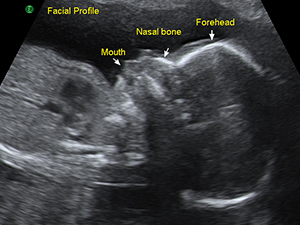

Facial profile in the first trimester

Facial profile in the second trimester